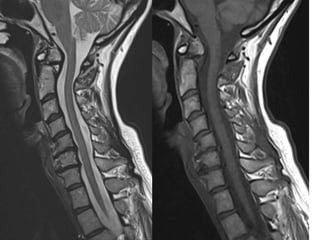

55 year old woman with central axial neck pain with

no radiculopathy; no signs or symptoms of myelopathy.

No history of trauma PMH: hypothyroidism in general

healthy

55 year oldwoman with central axial neck pain with no radiculopathy; no signs or symptoms of myelopathy. No history of trauma PMH: hypothyroidism in general healthy